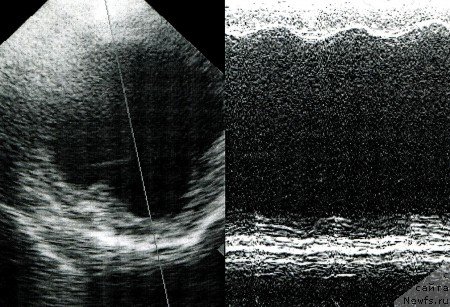

Эхокардиографическое исследование

При эхокардиографическом (ЭхоКГ) исследовании выявляют увеличение левых и правых отделов сердца, значительное снижение глобальной сократимости миокарда левого желудочка (уменьшение значений фракции выброса и фракции укорочения) (рис.6.). Доплерокардиография позволяет выявить относительную недостаточность митрального и трехстворчатого клапанов. У доберманов пинчеров размеры левого желудочка в норме несколько ниже, чем у собак других пород с массой тела 35-40 кг, поэтому конечно-диастолический размер (КДР) левого желудочка более 46 мм, и конечно-систолический размер (КСР) левого желудочка более 39 мм считают увеличенными. При выраженной стадии болезни и значительном расширении камер сердца эхокардиографическое исследование дает исчерпывающую диагностическую информацию, но если патология еще не достигла полного развития, то необходимо проведение дополнительных эхокардиографических исследований с применением тканевой доплерографии.

Рис. 6. ЭхоКГ собаки с ДКМП (В- и М- режимы). Значительное увеличение полости левого желудочка и снижение глобальной сократимости миокарда.

Рис. 7. ЭхоКГ собаки ДКМП. Значительное увеличение размеров полости левого предсердия.